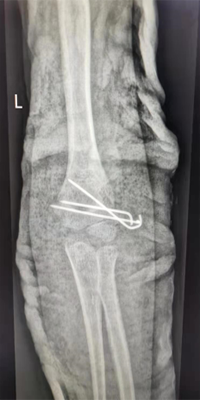

典型病例三

肱骨髁上骨折闭合复位交叉克氏针内固定术